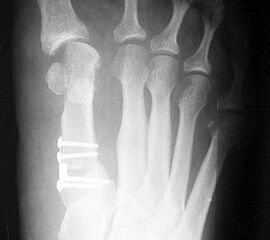

Die Röntgenaufnahmen (Abbildung 1) zeigen den Fuß einer 34 jährigen Patientin nach Exostosenabtragung. Der erhöhte intermetatarsale Winkel wurde durch eine alleinige Abtragung der Exostose nicht reduziert. Als weiterer Risikofaktor für ein Rezidiv liegt ein pathologischer Gelenkwinkel vor. Der intermetatarsale Winkel von 18 Grad kann durch eine basisnahe Osteotomie gut korrigiert werden. Da durch die gleichzeitige distale Korrektur des Gelenkflächenwinkels mithilfe einer Reverden-Green Osteotomie ein Längenverlust von ca. 2-4 mm einhergeht, bot sich als proximales Korrekturverfahren die basisnahe Open-wedge Osteotomie an, um bezüglich der Länge des Metatarsale I neutral zu bleiben (Abbildung 2). Die Kombination zweier verkürzender Verfahren (z.B. Lapidus und Reverden-Green) würden zu einem sehr kurzen ersten Strahl führen, mit dem Risiko einer Transfermetatarsalgie. Übersteigt die Verkürzung des Metatarsale I 2 mm, steigt das Risiko für die Entwicklung einer Transfermetatarsalgie deutlich an 8. Die durchgeführte Revision zeigt eine gute Stellung des 1. Strahls bei zentriert stehendem Gelenk.